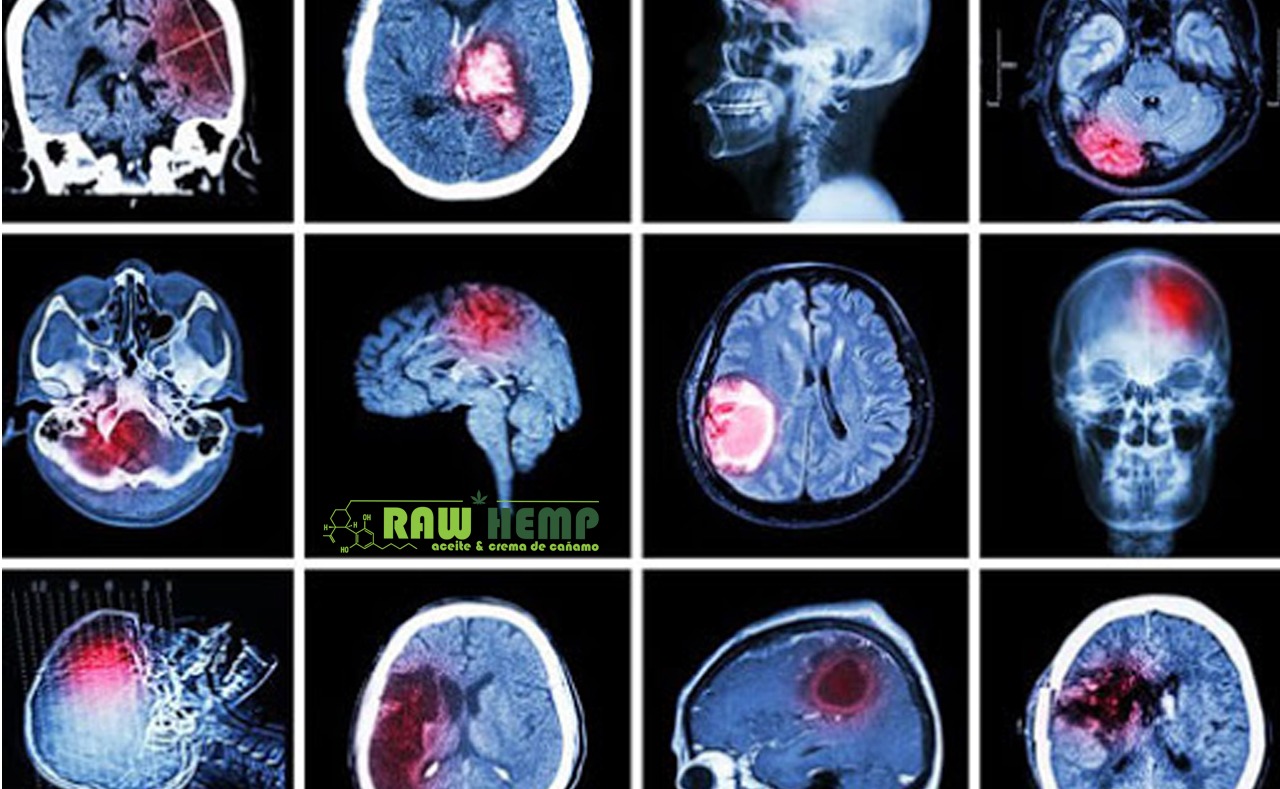

CANNABINOIDES PARA TRATAR TRAUMATISMOS CEREBRALES

Los traumatismos cerebrales pueden ser consecuencia de diversas razones, desde una conmoción leve hasta el coma. Dependiendo de en qué parte del cerebro se produzca el traumatismo, la víctima se verá afectada de una manera u otra. Este es un…